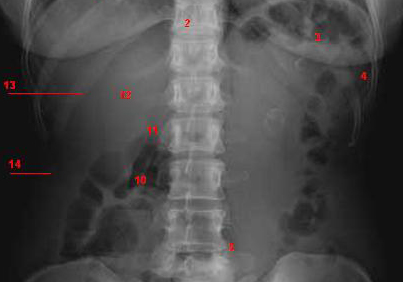

Image radiologique normale du foie :

Images radiologique

normale du cliche ASP de face :

-En haut ce sont les deux coupoles

diapragmatique limitant la cavite abdominale

- En bas c'est le pelvis |

- En haut et laterale ce sont des

dernieres cotes |

- Au centre : La region dorsolombaire , le rachis lombaire

et puis l'ombre des organe pleins : L'opacite du foie au

niveau de la region sous diphragmatique droite par

lobe droit et sous diapragmatique gauche par lobe

gauche , la bord inferieure du foie droit est

souvent a superieure de la crete iliacque droit . L'opacite de la rate est a gauche ,

sous diapragmatique gauche et externe . A inferieure

et pres de la colon vertebrale c'est l'ombre des

deux reins( l'ombre renale ) . L'opacite de deux

muscle de psoas peut en voyait de chaque cote de la

colonne lombaire au debut de D12 , L1 incline a deux

fosses iliaques . L'opacite de la vessie en se

voyait lorsqu'elle est en repletition ou en

semi-repletition |

| 1 Coupole diaphragmatique Dt |

| 2 Colonne vertebrale |

| 3 Gas dans gros tuberosite de

estomac |

| 4 Gaz situe dans l'angle colique

gauche |

| 5 Gaz du colon transverse |

| 6 Gaz du colon Sigmoide |

| 7 Saccrum |

| 8 Crete iliaque |

| 9 Tete femorale |

| 10 Gaz situe dans angle colique

droit |

| 11 Bord de silhouette de psoas |

| 12 Sombre du foie et rein droit |

| 13 onzieme cote |

| 14 Ligne graisseuse de la paroi de

abdomen |